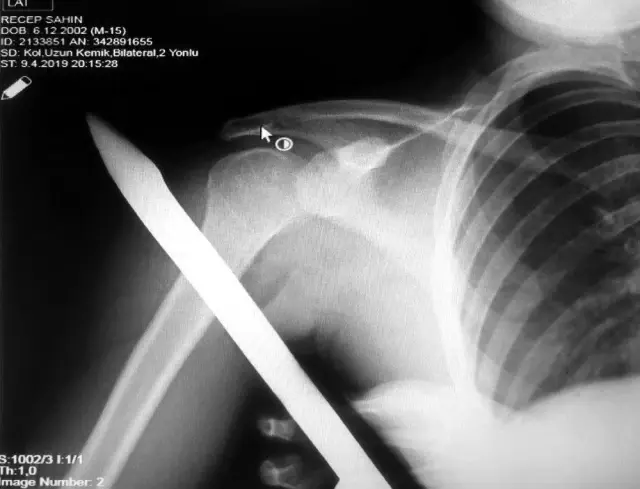

Asarcık ilçesi Emirmusa Mahallesinde dün meydana gelen olayda, Recep Şahin (17), cami çevresindeki korkulukların üzerinden atlarken ayağının kayması sonucu sivri uçlu demir omzuna saplandı. Demir, gencin omzunun arkasından girip ön kısmından çıktı. İhbar üzerine olay yerine gelen itfaiye, demiri keserek genci kurtardı. Genç, omzundaki demirle OMÜ Tıp Fakültesi Hastanesine kaldırıldı. Ortopedi ve Travmatoloji Uzmanı Prof. Dr. Turgut Nedim Karaismailoğlu tarafından yapılan başarılı operasyonla gencin omzundaki demir çıkarıldı.

Yaşadığı olayı anlatan Recep Şahin, "Caminin çevresindeki korkuluğun üzerinden atlarken ayağım kaydı. Korkuluk demiri omzuma saplandı. Demir omzumun arkasından girip önünden çıktı. Babamı aradım. İtfaiyeden yardım istedik. İtfaiye demiri kesti. Hastaneye kaldırıldım" dedi.

OMÜ Tıp Fakültesi Öğretim Üyesi Prof. Dr. Turgut Nedim Karaismailoğlu ise "Hastamızın ayağı kaymış ve korkuluk demiri omzuna saplanmış, arkadan girip önden çıkmış. Geldiğinde demirin ucu dışarıdaydı. Omzuna hasar vermiş. Demiri omzuna zarar vermeden çıkardık. Damar ve sinir problemi olmadan hallettik. Bu korkuluk demirlerinin daha dikkatli yapılması gerekiyor. Sivri uçlu olduklarından böyle vakalar olabiliyor. Vatandaşlarımız bu konuda dikkatli olmalı" diye konuştu.